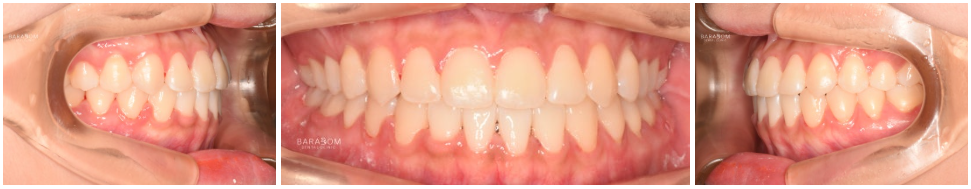

| 종결

치료를 받은 지 17개월 가량이 지난 후 모습입니다.

1️⃣반대 및 절단 교합 양상이

모두 해소되었으며,

2️⃣골격적인 문제의 한계를 넘어

아랫턱과 윗턱이 조화를

이루는 모습이 관찰됩니다.

또한 윗니가 아랫니를 덮으며

정상적인 피개량을 가지고 있는데요,

하악 전체 치열 후방 이동과

상악 앞니의 정출을 통해

교합의 안정과 함께

심미를 되찾은 모습입니다.